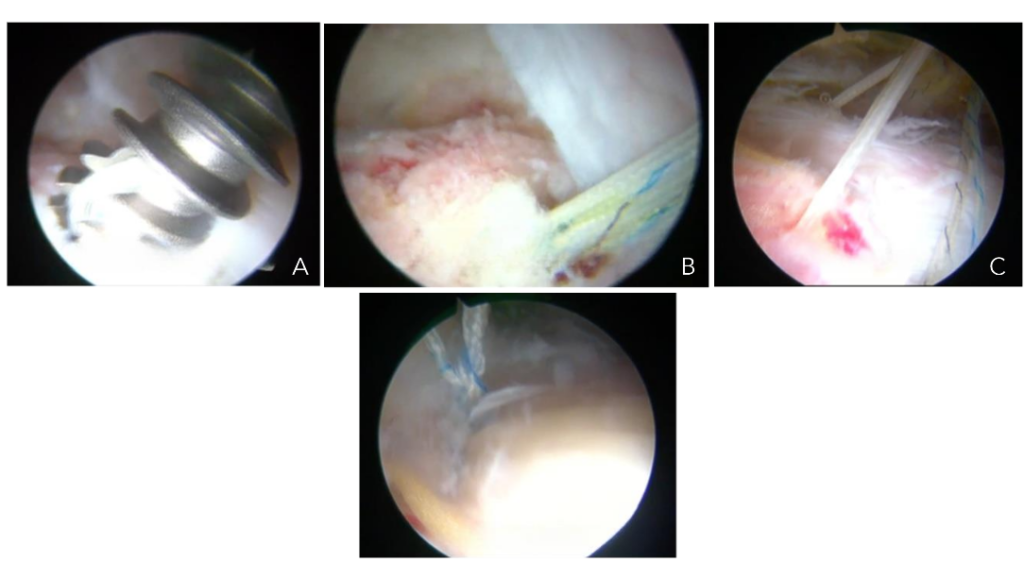

Complete rupture of the gluteus medius tendon presents a significant challenge for surgeons, as the tendon has been displaced from its anatomical position in the greater trochanter, which is typically sclerotic and is associated with a tendon of poor quality. Poor outcomes have been reported with conventional open surgical treatments in such cases. Consequently, we have developed an endoscopic surgical technique, as described for partial tendon lesions, with the notable distinction that in these cases it is crucial to examine the continuity of the tendon with the bone tissue and assess its adherence or detachment. If the tendon is detached, it must be incised longitudinally to identify the sclerotic zone of the bone at the greater trochanter, which is then removed, typically with a 5.5 mm burr drill, to create a bleeding bed where the tendon can heal. The tendon is subsequently fixed with one or two 5.5 mm titanium anchors loaded with double sutures to close the incision and secure the tendon to the bleeding bed of the greater trochanter Figure 9a-c and 10a-d.

Figures 9a-c. Endoscopic view of a longitudinal incision of the gluteus medius tendon (A), exposure of sclerotic bone beneath the tendon (B), bone bed preparation under tendon (C).

Figures 10a-d. Endoscopic view of a gluteus medius tear repair. Placement of a titanium anchor (A) Anchor in bone with sutures (B). Anchor sutures through tendon closing longitudinal incision/ tear (C). Final suture-anchor construct (D).